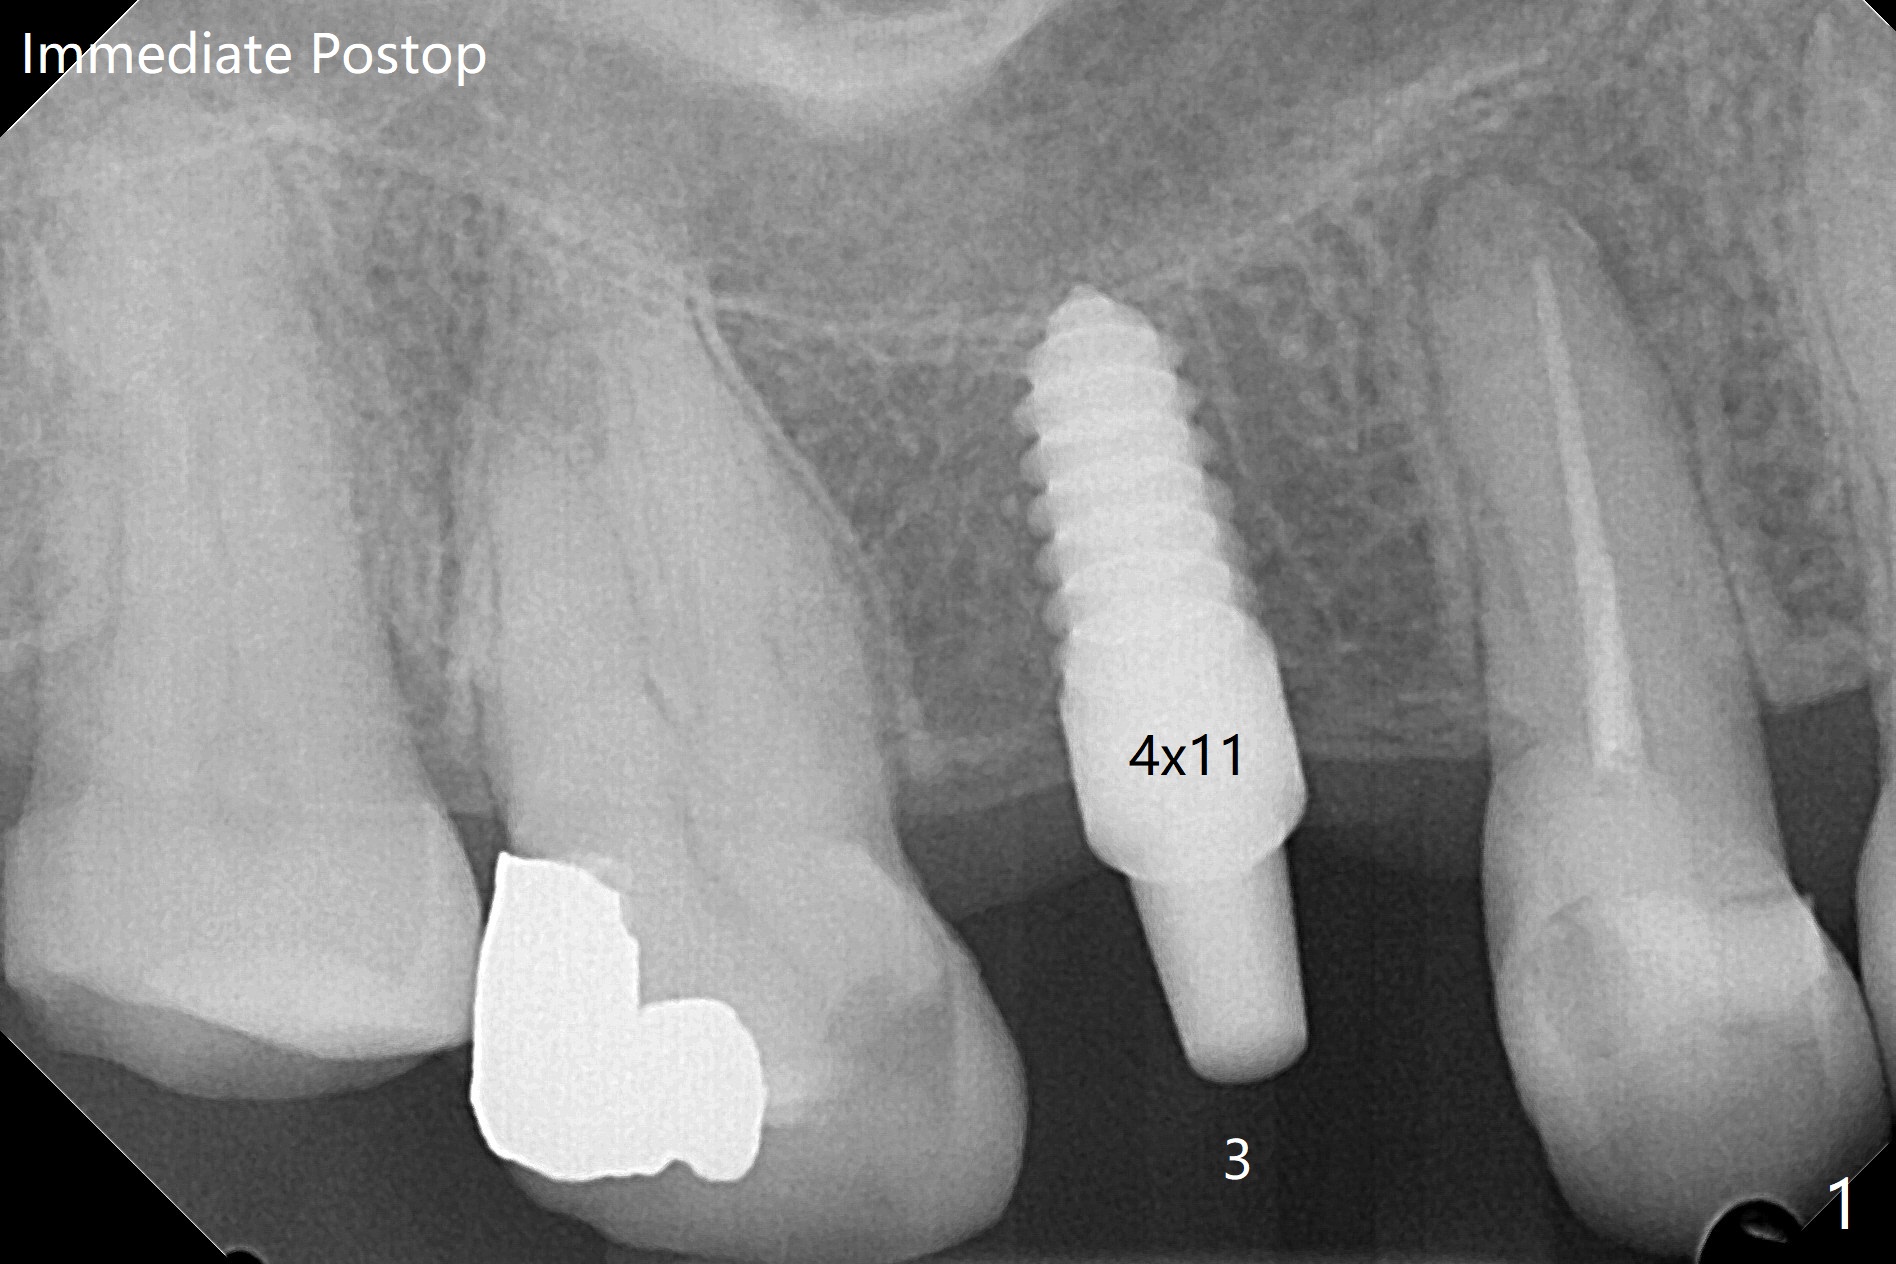

81岁女缺失3,29-31号牙,准备在3,29,31位点种植,大约术后3-4个月做3牙冠,29-31桥。为了简化治疗,选择一段式植体,牙槽嵴不宽裕。为了减少并发症,第一,植体有前后自然牙保护,第二,植体直径不是太小,第三,在导板指引下,植体方位基本正常(图一至四)。上颌缺牙区角化龈宽,使用环形刀,而下颌角化龈窄,切开种植,之后植骨(图四:箭头)。由于上颌骨质稀疏,上颌植体扭力低,暂时不做临时修复。为了降低植体微动,术后降低29,31基台高度(比较图三,图四)。最后利用基台固定牙周敷料。